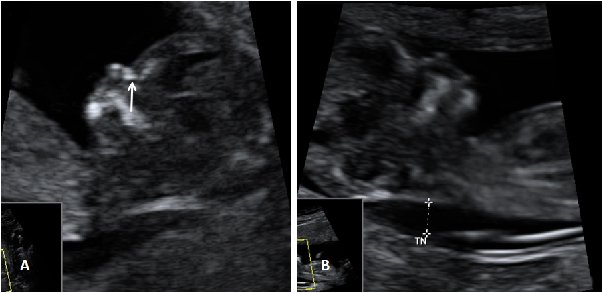

En la semana 12 de gestación, la embarazada aún no nota los movimientos del bebé que crece dentro de su útero. Pero en esta ecografía en 4D se observa sus vigorosos movimientos.

Ecografía 4D de feto de 12 semanas de espaldas

La curiosa ecografía de este feto de 12 semanas comienza con la imagen de espaldas. El niño se gira hasta colocarse de perfil y es entonces cuando empieza a mover brazos y piernas con agilidad. Todo un signo de bienestar fetal.